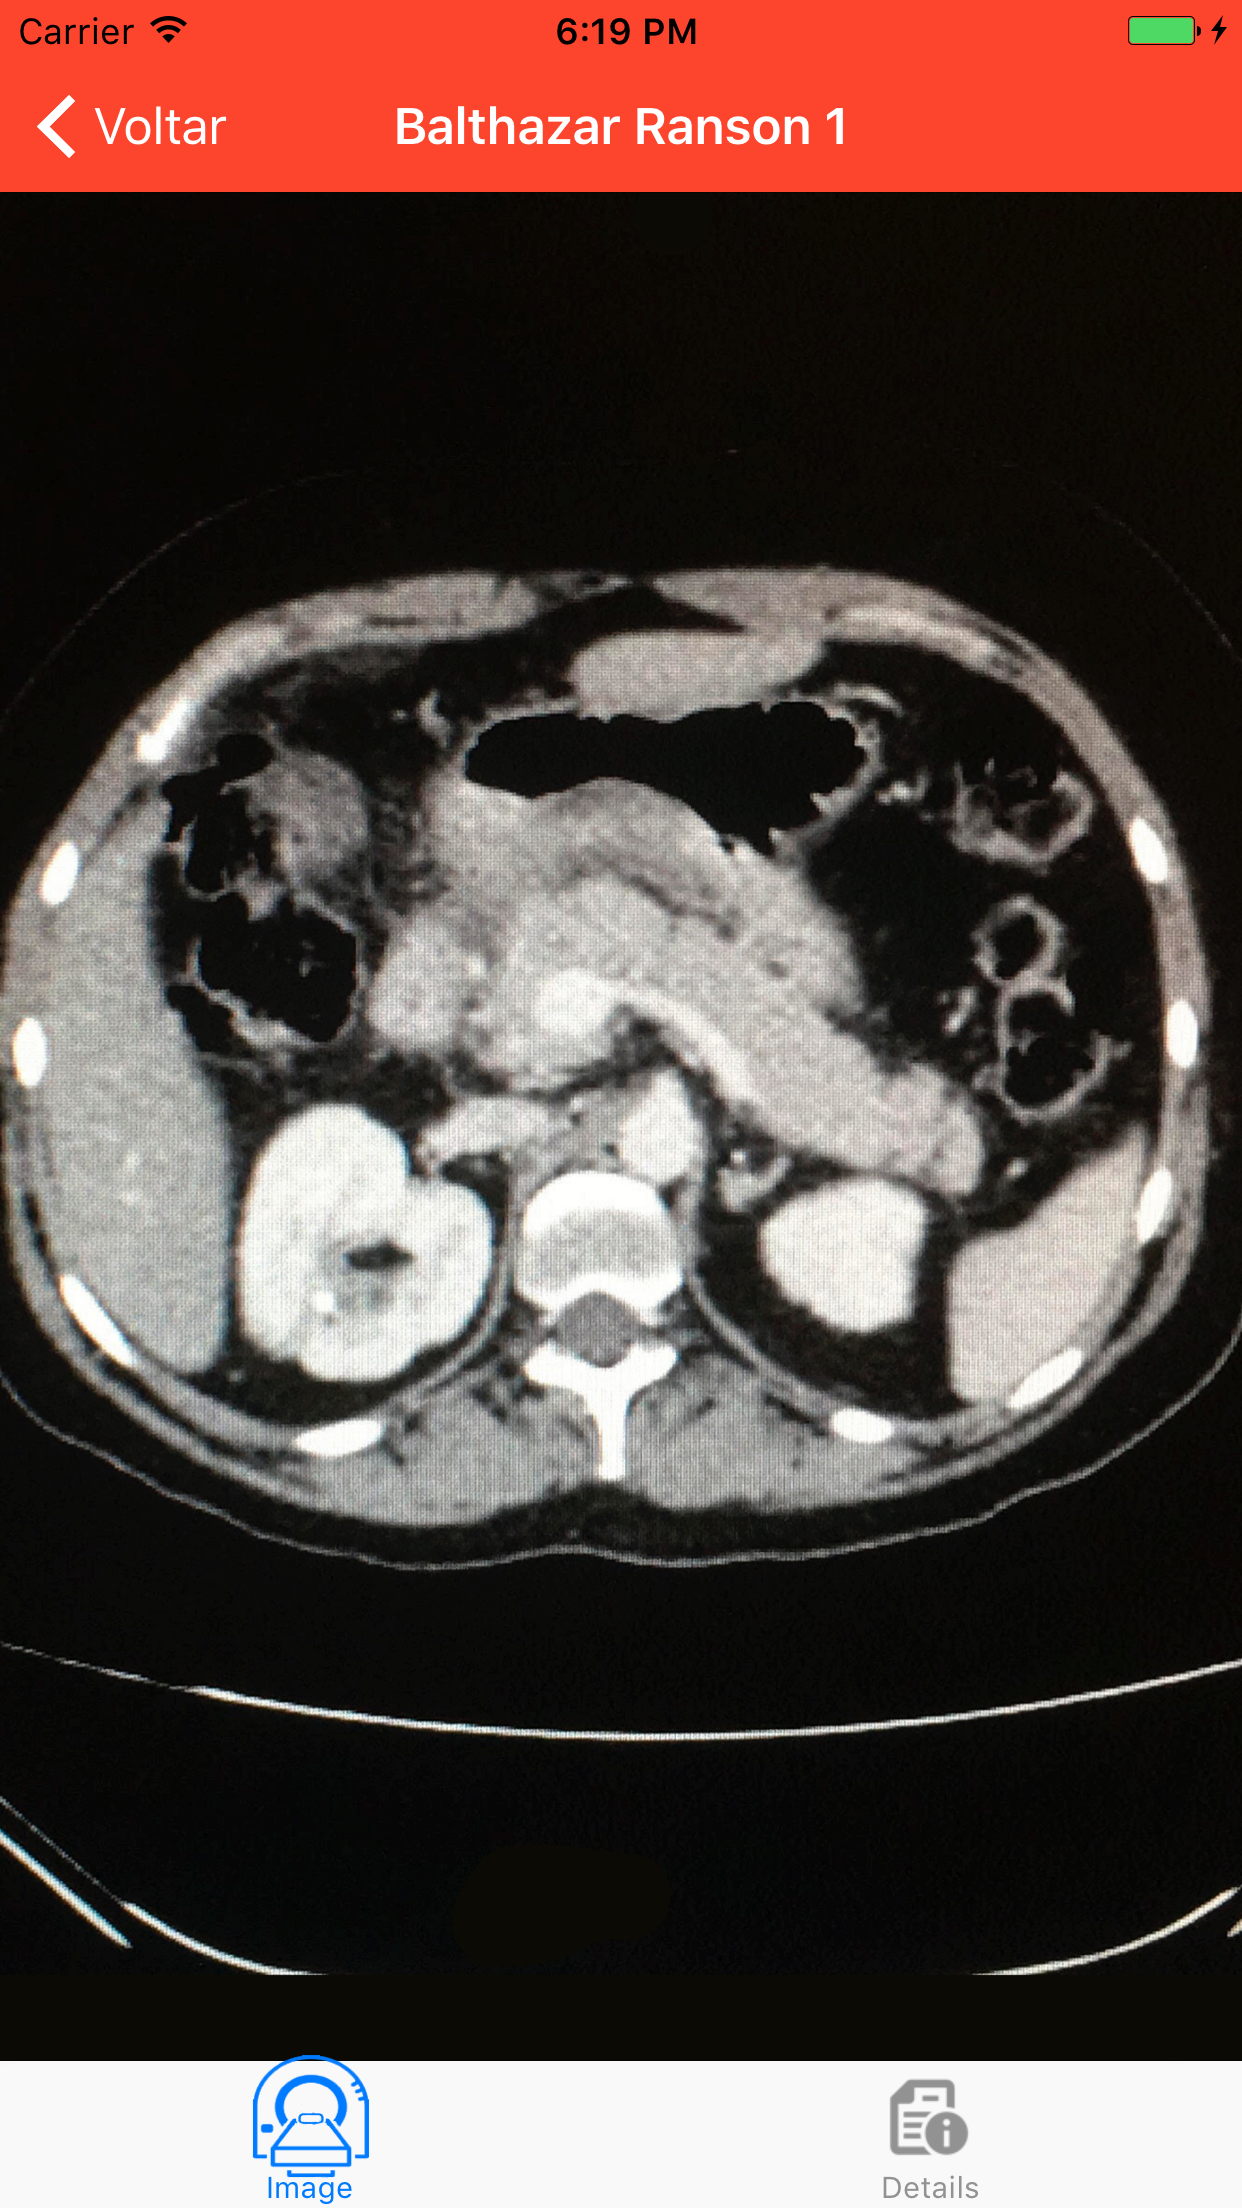

This application was developed by Acute Pancreatitis Study Group of Santa Casa de de São Paulo School of Medicine, in order to make the diagnosis, monitoring and treatment of acute pancreatitis easier, accessible and standardized, avoiding complications of this disease. The content information of this application was based on the management of acute pancreatitis at the Central Emergency of Santa Casa de São Paulo, available at “Pancreatite Aguda” from Tercio de Campos and Samir Rassian, and the American College of Gastroenterology Guideline for management of acute pancreatitis (2013), which can be found at “Full Guideline”, on the main screen of this application. Resource: - Diagnostic criteria - Calculators major severity scores (Apache II, SOFA, Modified Marshall, Atlanta 2013, Severity determinants, Ranson, Balthazar-Ranson) - Indications of specific tests - CT Images Organization: Study group of Acute pancreatitis of Faculdade de Ciências Médicas da Santa Casa de São Paulo Idealization: Dr. Tercio de Campos Realization: Angelo Chelotti Duarte Contribution: Aline Celeghini Rosa Vicente (overall coordination), Vitor Minari Campos, Rodrigo de Almeida Mastrorosa, Bruna do Nascimento Santos Support: Centro Acadêmico Manoel de Abreu --WARNING-- The information provided by this app is solely at your own risk. The authors disclaim responsibility for any injury to persons resulting from use of this app.